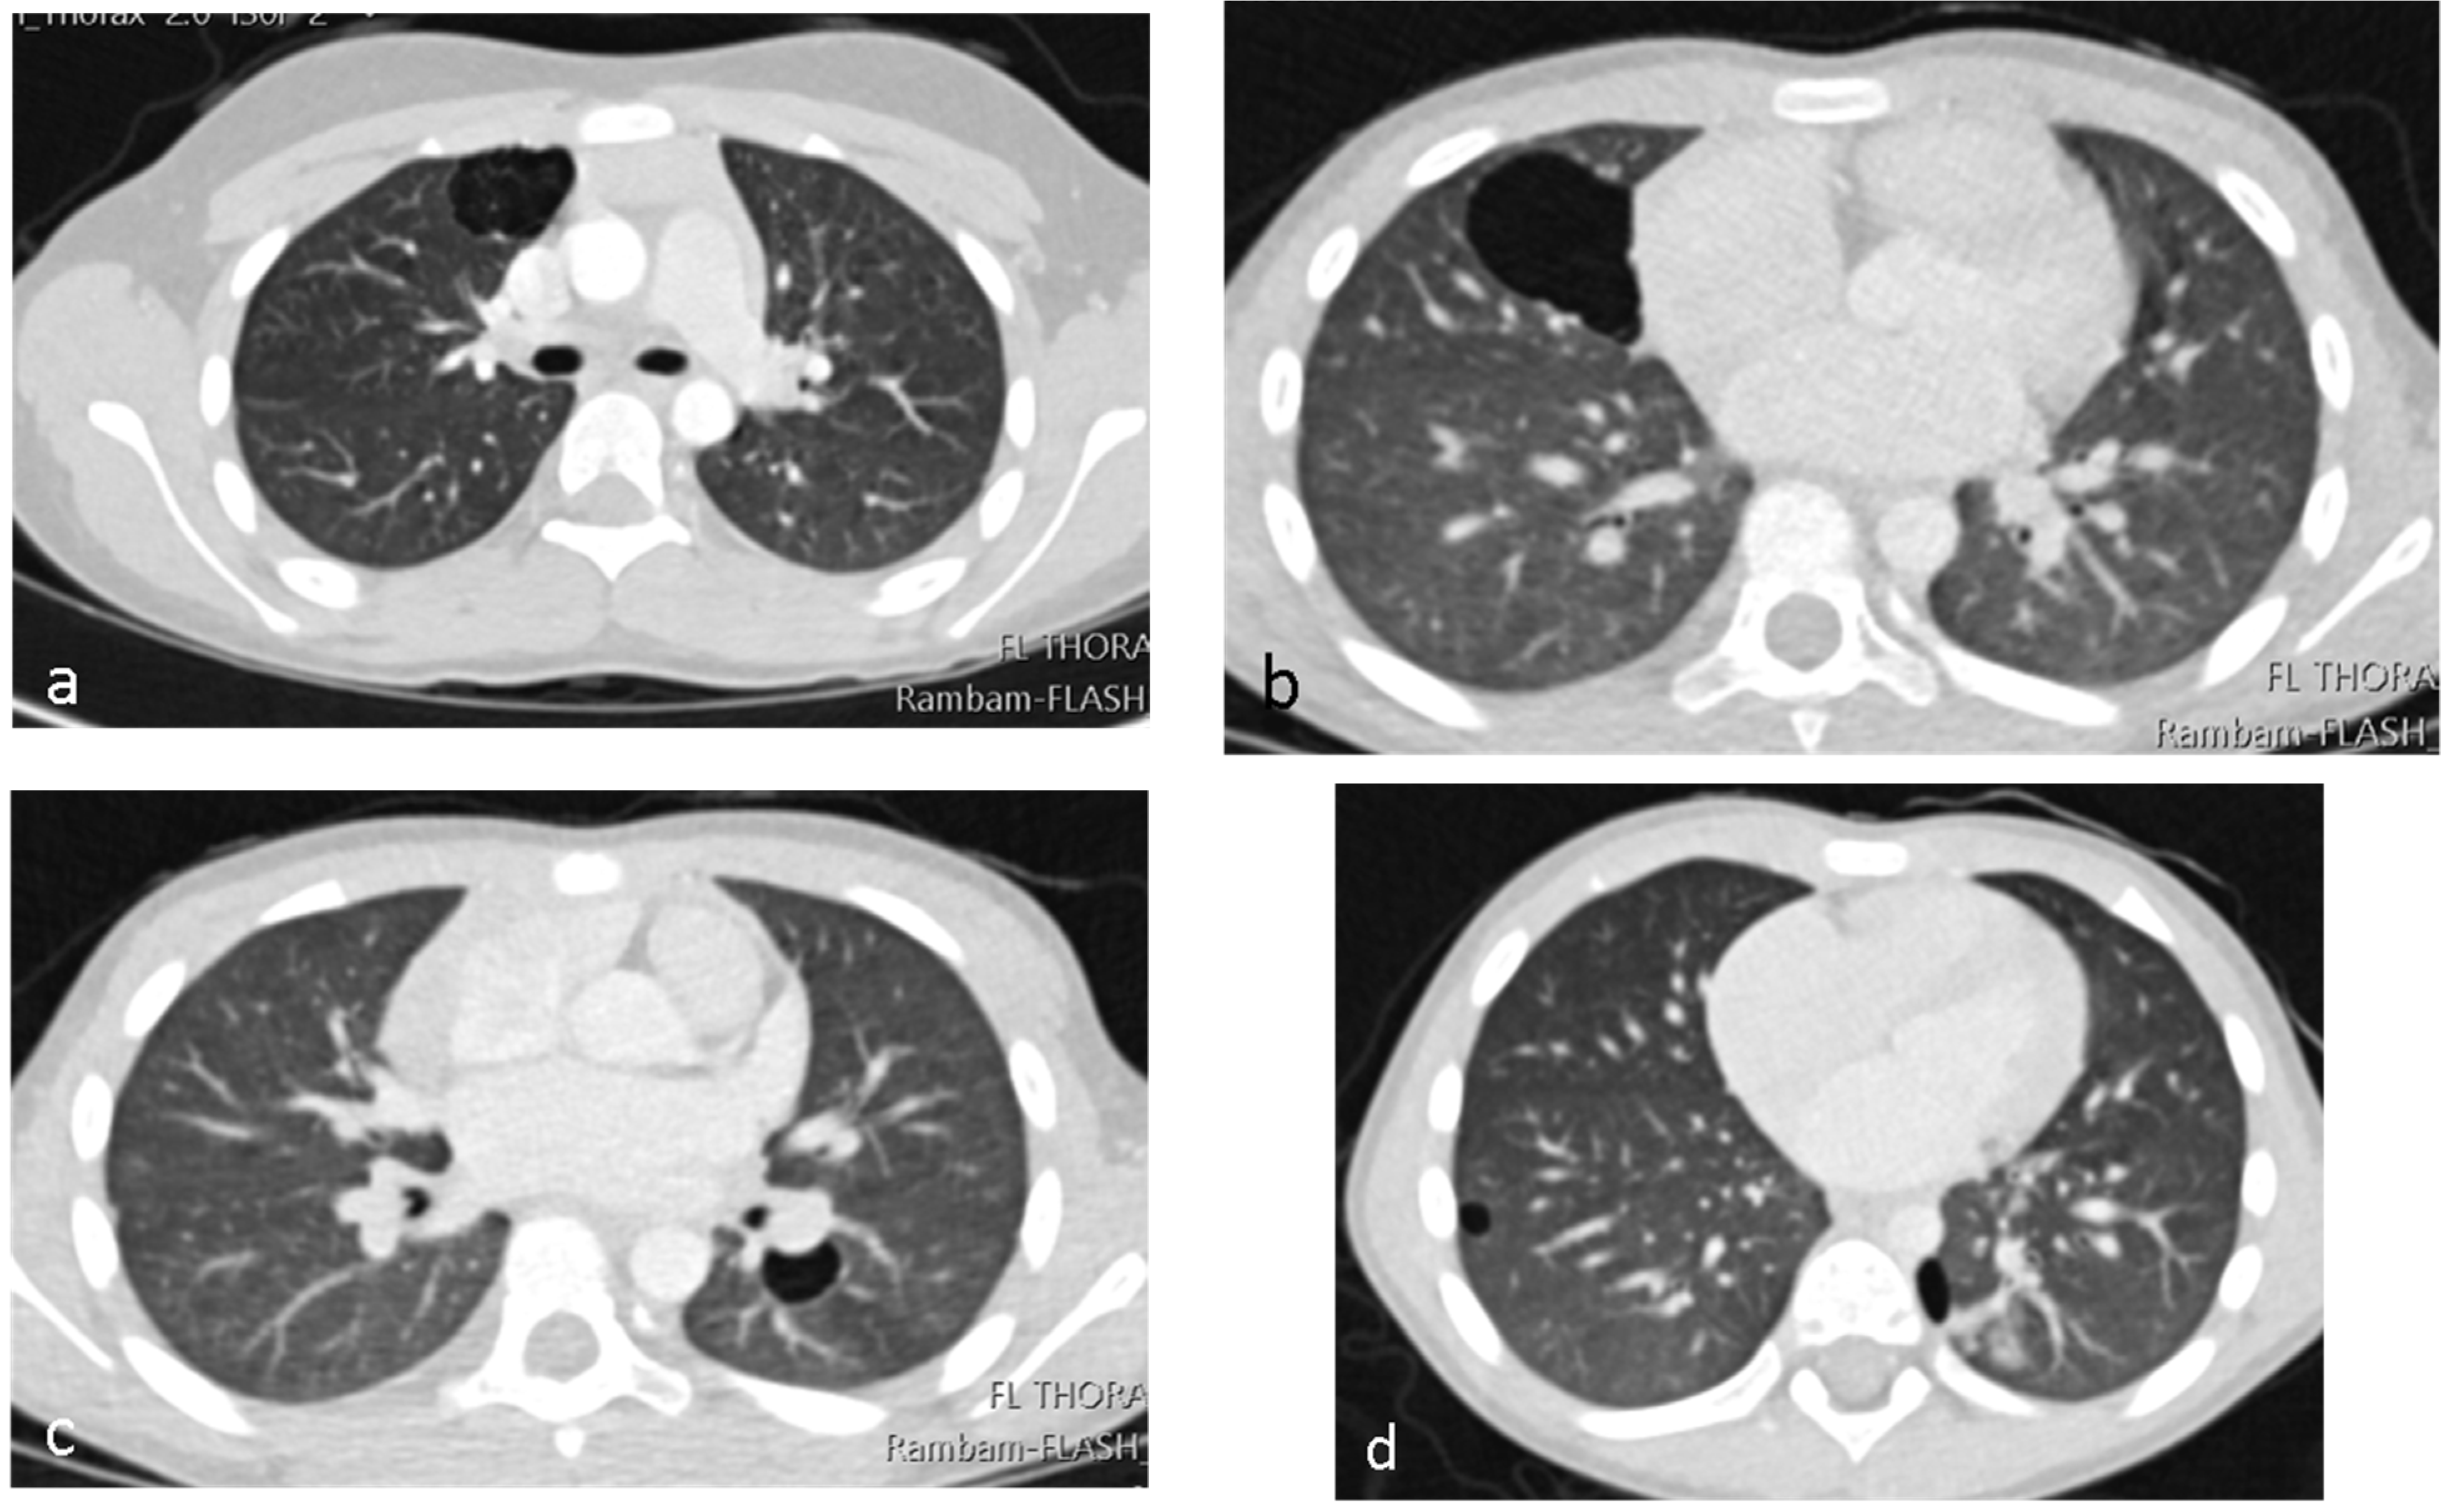

A 3-year-old healthy boy experienced increasing weakness and shortness of breath several weeks after a febrile upper-respiratory disease. He lost 1 kg of weight. A chest X-ray performed in the community showed complete opacification of the right hemithorax (Figure 4a), and he was referred to the hospital. A chest CTA revealed a large tumor occupying most of the right hemithorax, without any aeration of the lung (Figure 4b). Most of the tumor was solid hypodense tissue, with some cysts on the periphery. An ultrasound study was able to better delineate the multicystic hemorrhagic nature of the tumor (Figure 4c). A biopsy was taken under sonographic guidance and the pathologic diagnosis was type II PPB with foci of RMS (rhabdomyosarcoma). The DICER1 germline was positive, and staging with FDG PET-CT (2-[(18)F]-fluoro-2-deoxy-d-glucose positron emission tomography-computed tomography showed no metastases (Figure 5). The tumor was unresectable, and the patient received neoadjuvant chemotherapy with IVADo (Ifosfamide, vincristine, actinomycin-D, and doxorubicin) followed by resection of the tumor, which was pleural based. He received completion chemotherapy of up to 12 courses. There was 80% tumor necrosis in the final specimen. After 3 years of follow up, both clinical and with CTA, there is no recurrence (Figure 4d). The DICER1 germline mutation was positive in the patient’s father and in his three siblings. The siblings were all asymptomatic. They all underwent CTA of the chest, with the following findings:

Nine-year-old girl (the older sister of patient no 3): complex cystic lesion with aberrant vessels within the cyst septa located in the right upper lobe (Figure 6a). We suspected that this lesion might be PPB, and consulted the International Pleuropulmonary Blastoma registry team. They agreed, and suggested lobectomy.

Six-year-old boy (older brother of patient no 3): two purely cystic lesions, one in the right middle lobe (diameter of 4 cm) and a smaller cyst in the left lower lobe (Figure 6b,c).

Fifteen-month-old boy (younger brother of patient no 3): two purely cystic lesions, one in the right lower lobe (diameter of 0.6 cm) and a second cyst (diameter of 1 cm) in the left lower lobe (Figure 6d).

We consulted the IPPBR team about the other three siblings as well; they considered the lesions to be a type I PPB, and resection was suggested.

The parents were given the complete information about the findings and the consultations. They decided to proceed with a more conservative approach, with clinical and radiological follow up only. Two years later, the children are healthy, and the radiological findings are stable.

Figure 6. Asymptomatic DICER1-germline-positive siblings of index patient number 3. Axial images of Chest CTA: (a) Nine-year-old girl with RUL anterior multiseptated cystic lesion. (b,c) Six-year-old boy with right and left cystic lesion. (d) Fifteen-month-old boy with bilateral, small cystic lesions.